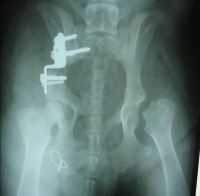

Рентгеновский снимок после операций. ТБ суставы метиса овчарки до и после операции заметно значительное увеличение покрытия головки бедренной кости вертлужной впадиной

thumb 035  thumb 036